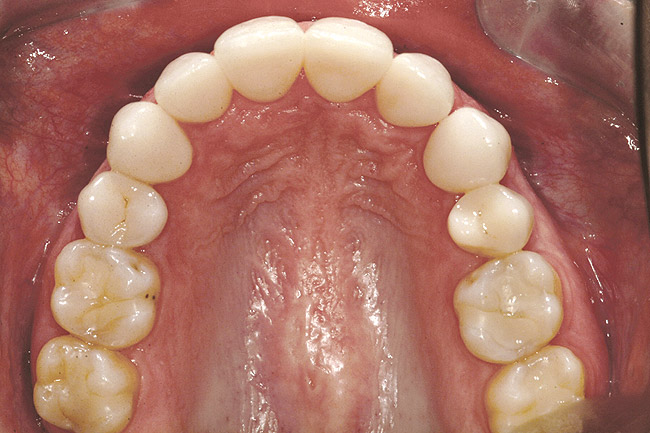

Fig 6 (and Fig 7). Prerestorative orthodontics was completed in 5 months. Final result 3 years, 4 months after completion.

Figure 6

Fig 8 (and Fig 9). Teeth Nos. 5 and 12 were converted to Nos. 6 and 11, and Nos. 6 and 11 were converted to Nos. 7 and 10. Nos. 4 and 13 were enlarged. Note stability and absence of orthodontic relapse. Before-and-after smiles. Periodontist: Edward P. Allen, DDS, PhD. Prosthodontist: Robert R. Winter, DDS.

Figure 8